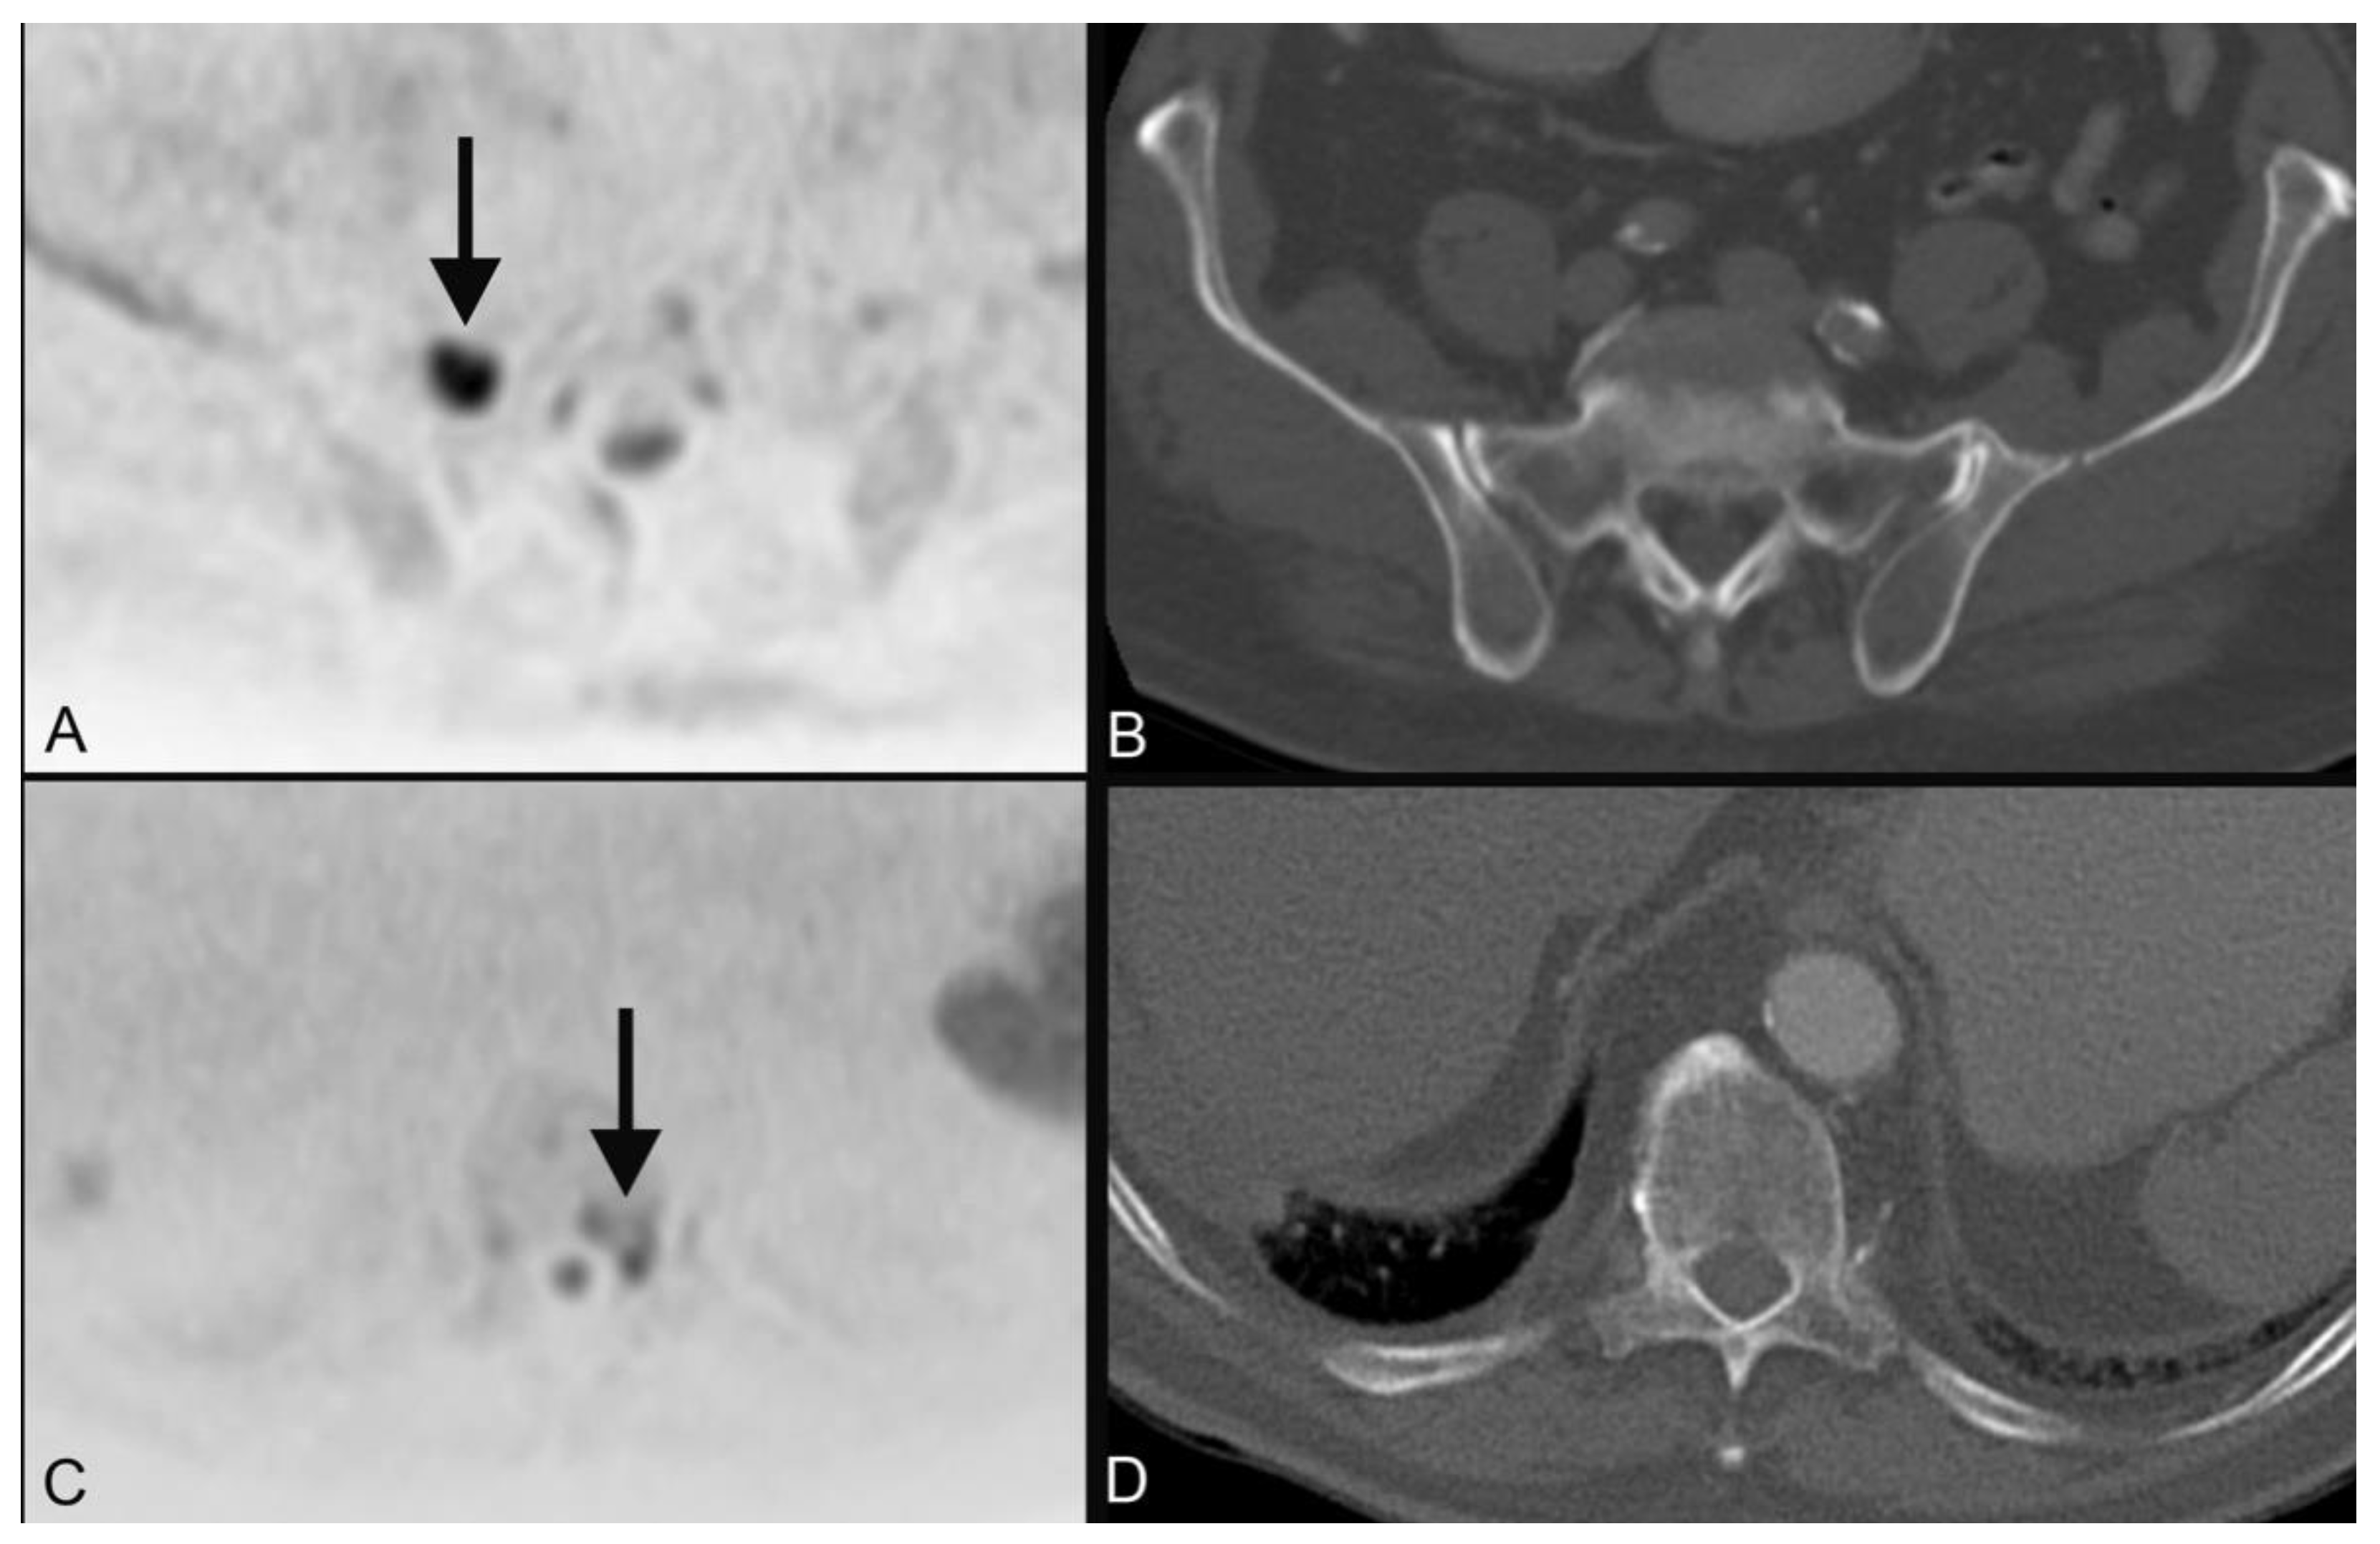

| 1 | plasmocytoma (Figure 3) | ||

| 4 | bronchial carcinoma (Figure 4) | ||